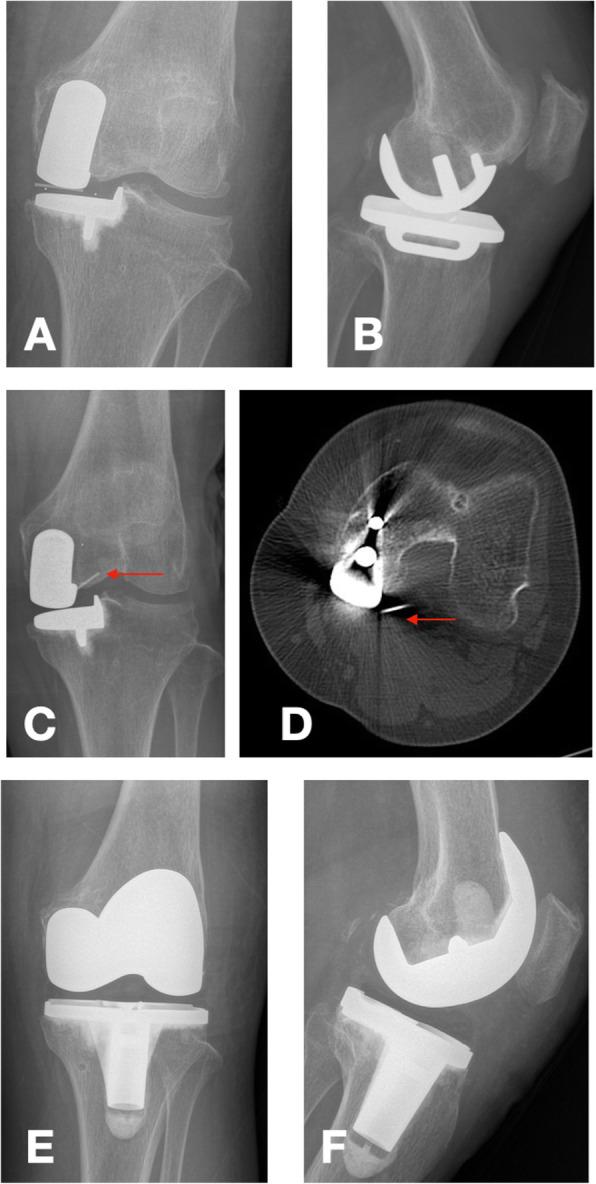

The use of Oxford Unicompartmental Knee Arthroplasty (UKA) has increased rapidly in both Western and Asian populations, with excellent functional outcomes and high patient satisfaction. While previous evidence regarding clinical outcomes and survival rates after Oxford UKA was based on studies in Western populations, the results may be different in Asian patients. The relevance of age for postoperative function after Oxford UKA also remains unclear. Hence, the aim of our study was to clarify the effectiveness and safety of Oxford UKA in Asian patients aged over 80 years.

METHODS

A retrospective review was performed and included 195 patients (209 knees) who underwent an Oxford UKA between June 2015 and July 2018. We divided the patients into three groups by age: Group 1, 60-69 years; Group 2, 70-79 years; and Group 3, over 80 years. We used the Hospital for Special Surgery (HSS) score and Western Ontario and McMaster (WOMAC) Universities Osteoarthritis Index score to evaluate the general condition of the patients' knees before surgery and at last follow-up. We also recorded perioperative and short-term complications.

Group 1 consisted of 60 patients (60 knees); Group 2, 70 patients (79 knees); and Group 3, 65 patients (70 knees). The mean follow-up was 21.34 ± 12.04, 22.08 ± 11.38, and 21.76 ± 10.20 months in groups 1, 2, and 3, respectively. At last follow-up, the patients in Group 3 showed lower function scores compared to groups 1 and 2 (P < 0.05), but the HSS scores and the WOMAC scores were significantly improved in all three groups. In terms of perioperative and other complications, the three age groups did not differ significantly.

CONCLUSION

Oxford UKA is an effective and safe treatment for osteoarthritis, even in elderly patients in China. Elderly patients have lower knee function scores than younger patients. However, the knee joint pain of the elderly patients was relieved and function improved compared to the preoperative condition.